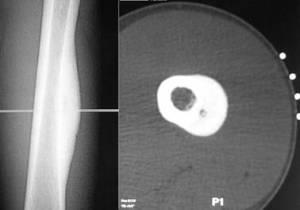

Остеохондрома

Остеохондрома – это доброкачественная шишка на спине на позвоночнике, образовавшаяся из костной ткани. Диагностируется в возрасте 10-ти – 25-ти лет.

Симптомы обычно отсутствуют. Можно случайно прощупать шишку на спине. Если она сильно разрастается, то сдавливает нервы, мышечную ткань. Вследствие этого наблюдаются различные проблемы с двигательной активностью, чувственностью и пр. Имеют место переломы, инфаркты, тромбозы. Шишка на спине не болит.

Лечат остеохордому ортопеды – хирургически. Показан радикальный метод тогда, когда опухоль существенно деформирует скелет и имеет большой размер.

Наркоз предварительно делается общий. После специалист удаляет образование и основание ножки. От костной пластики можно воздержаться.